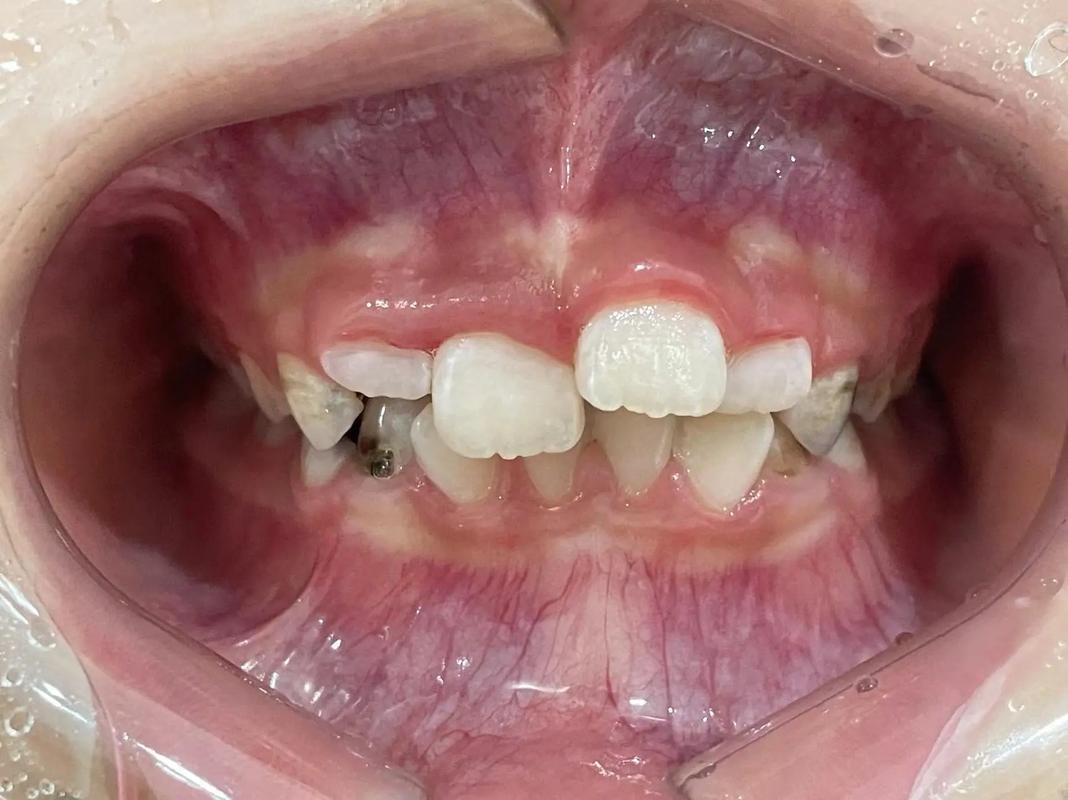

牙齿单侧正畸补缺齿是一种针对单侧牙齿缺失后,通过正畸技术调整牙齿位置、恢复咬合功能与面部美观的综合治疗方案,单侧缺齿在临床上较为常见,可能由先天缺失、外伤、严重龋齿拔除等原因导致,若不及时干预,可能引发一系列口腔问题:缺牙间隙两侧的邻牙会向缺隙倾斜移位,对颌牙会因失去咬合接触而伸长,导致咬合紊乱;长期偏侧咀嚼会使咀嚼肌力量失衡,可能引发颞下颌关节疾病;牙齿移位还会影响面部对称性,甚至导致发音不清,正畸补缺齿通过系统性治疗,既能解决牙齿排列问题,又能为后续修复(如种植牙、烤瓷牙等)创造条件,实现功能与美观的双重恢复。

单侧缺齿的治疗并非简单“补牙”,而是需要通过正畸手段调整整个牙列的动态平衡,其核心逻辑在于:通过正畸移动牙齿,关闭或调整缺牙间隙,为修复体提供足够且合适的位置;纠正因缺牙导致的咬合异常,恢复正常的咀嚼功能;改善牙齿排列与面部美观,避免长期并发症,治疗目标可概括为三点:一是恢复牙齿的正常排列与咬合关系,二是建立稳定的咀嚼功能,三是维持面部对称与口腔健康。

对于缺牙间隙较大的患者,若直接进行种植修复,可能需要通过正畸将邻牙向缺隙移动以缩小间隙,或通过远中移动牙齿为种植提供骨量;而对于缺牙间隙较小但邻牙倾斜的患者,则需要先直立倾斜的牙齿,再进行修复,正畸与修复的协同设计,是确保治疗效果长期稳定的关键。